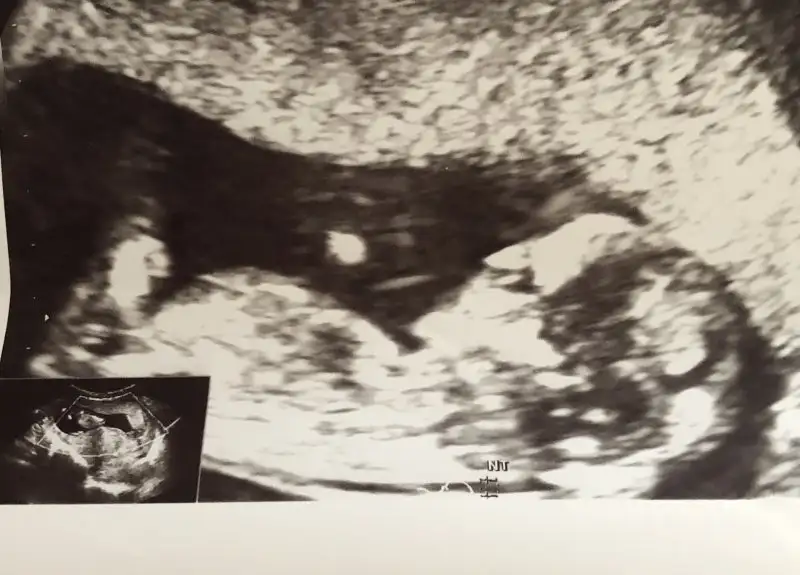

- 9 Nisan 2015

- 2.390

- 3.486

- 83

- 39